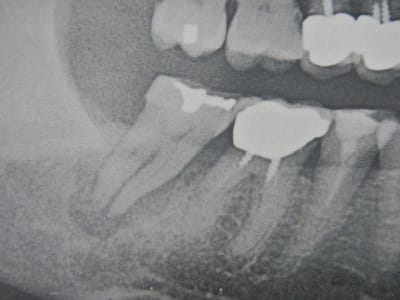

-extraction de 47 et curetage de l'alveole en Décembre 2011 (voir cliché sur panorex )

-Scanner fait en Mai 2012: panne de l'imprimante de papier radio du radiologue, il me donne une copie sur papier avec inversion des couleurs: noir pour blanc et l'inverse, je ne me méfie pas, fait l'étude pour la mise en place de l'implant.

-Mise en place de l'implant 4.6 X 8mm :très peu de couple d'insertion mais l'implant est stable: je peux visser la vis de cica sans problème.

-Radio de contrôle et là je découvre cette image en bout de l'implant qui est le granulome qui était présent sous la 47.

Il ne s'agit peut-être que de l'image cicatriciel hypodense de la lésion.

Il faut du temps pour que radiologiquement ça disparaisse !